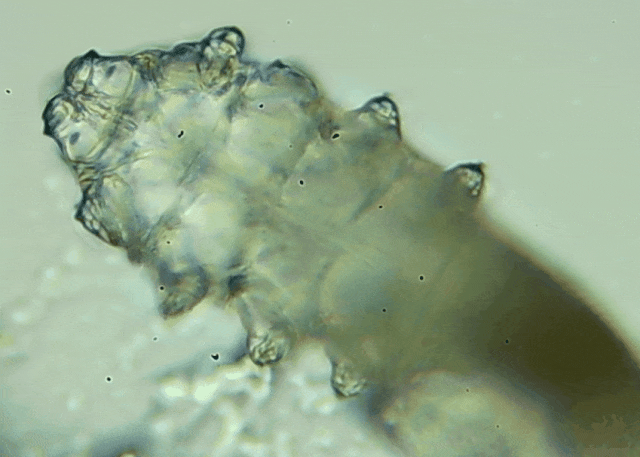

眼瞼位于眼球前面,分為上下眼瞼,而睫毛、一些腺體的開口和淚小點都在眼瞼邊緣,也就是瞼緣上。蠕形螨是一種寄生于毛孔、腺管和瞼緣上的螨蟲,因為體型微小,肉眼無法察覺。...[詳細]

我只是眼睛癢,結(jié)果醫(yī)生說我睫毛里有80只蟲?這不是恐怖片,而是真實的病例:武漢一13歲男孩,右眼9根睫毛里檢出39只螨蟲,左眼9根里檢出47只。 而且這不是極端個案,廈門眼科中...

我只是眼睛癢,結(jié)果醫(yī)生說我睫毛里有80只蟲?這不是恐怖片,而是真實的病例:武漢一13歲男孩,右眼9根睫毛里檢出39只螨蟲,左眼9根里檢出47只。 而且這不是極端個案,廈門眼科中...[詳細]